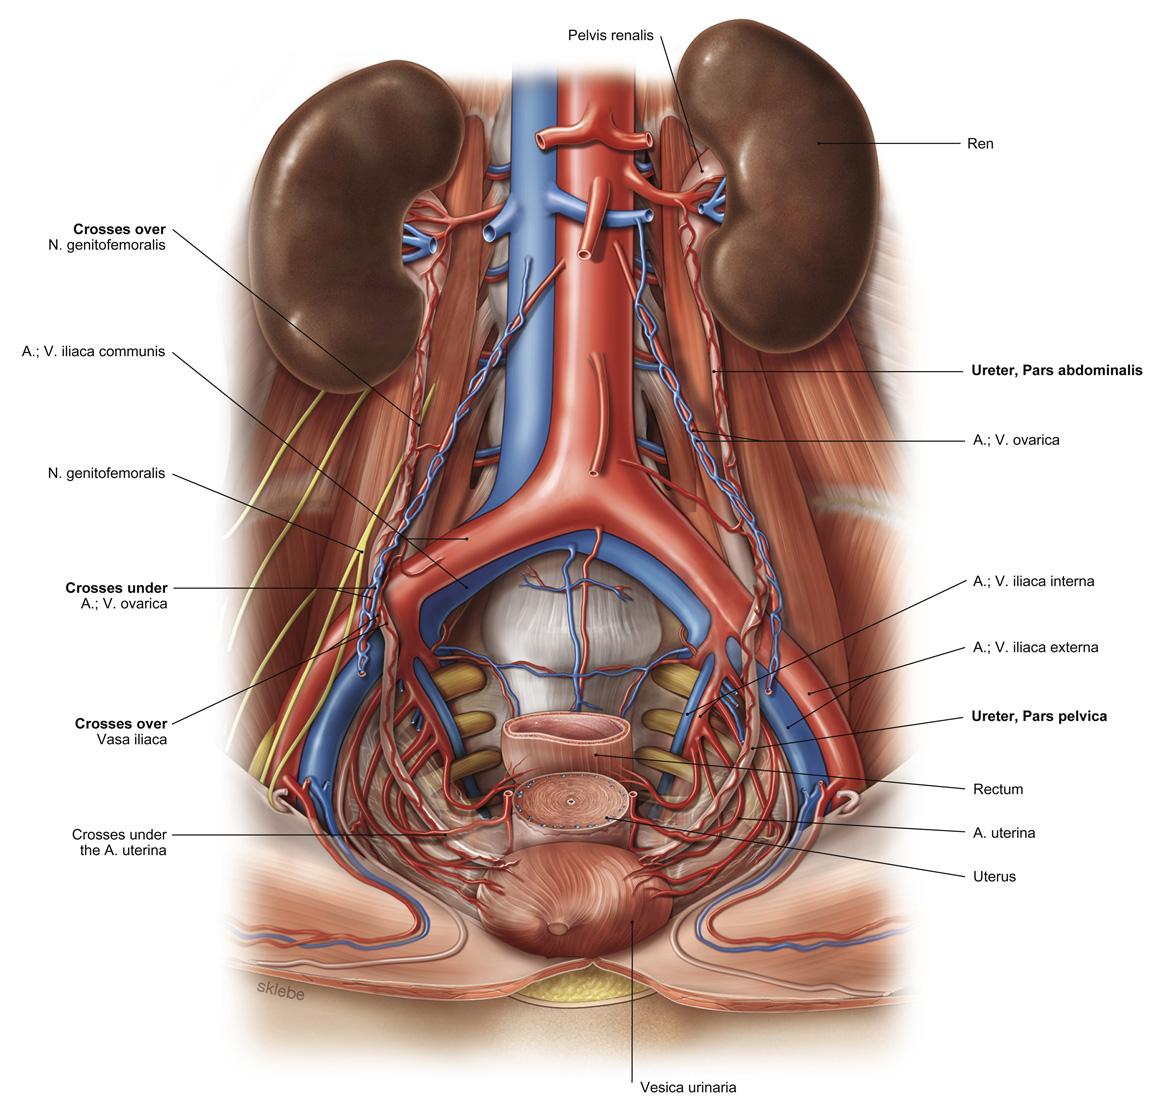

Fig 3.26: a. iliaca communis

|

|